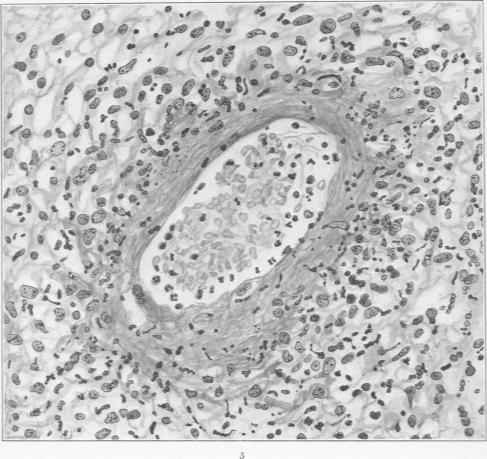

Specific Lesions of Peripheral Blood Vessels in Rheumatism.

Am J Pathol. 1926 May;2(3):235-250.11.